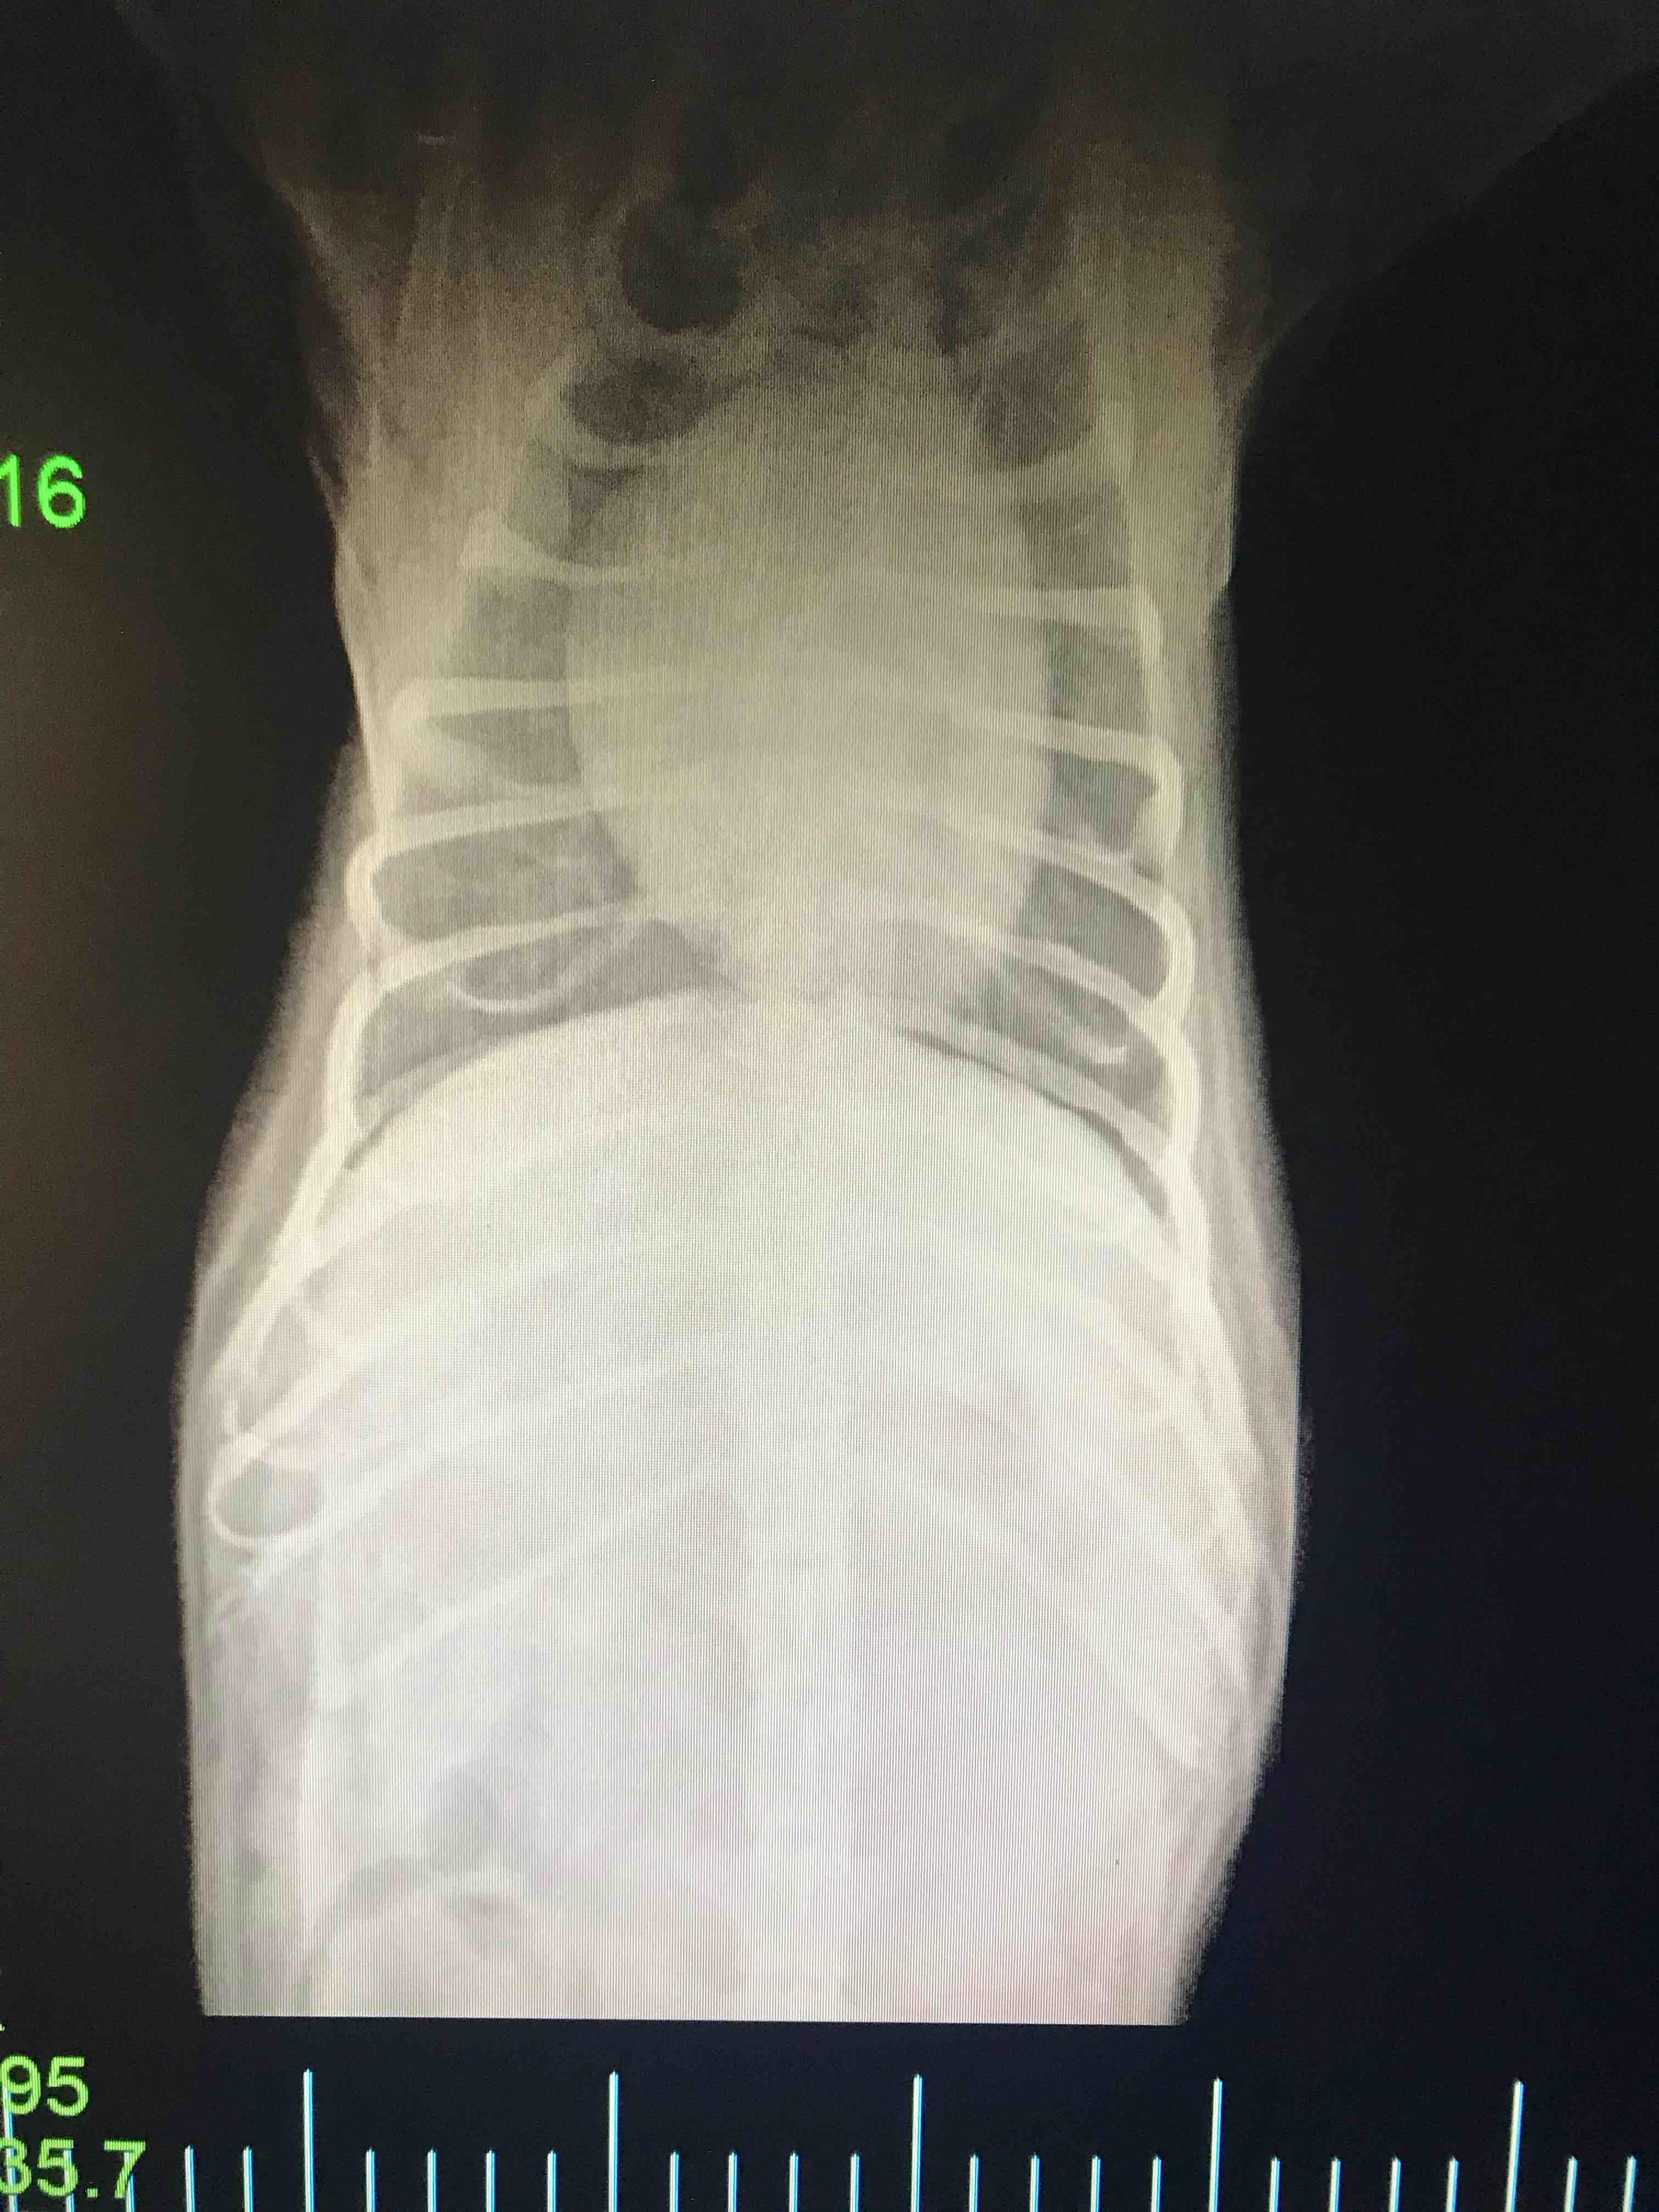

Pet's info: Dog | Mixed Breed | Male | neutered | 2 years and 3 months old | 20.08 lbs

Last question I posted, someone said I needed a VD of the heart. Here it is. I had one doc said his heart look bad and he recommended a ultrasound. second opinion said he looks normal and a third said his head looked ehhhhh. I don’t know who to believe. So here I am. How does his heart look? Does it look normal? Reason for this, He’s been getting tired more easily and takes more breaks.

I don’t think the heart looks terribly enlarged, maybe on the big side of normal. Ask the vet who took the rads if they are able to submit them to a radiologist for review. (A radiologist is a vet who spent at least 3 additional years to do a residency to specialize and study only imaging. Their expertise is really valuable in cases that are not clear cut and obvious.) If his lab work is all normal, and a radiologist is concerned about the appearance of the heart, then it’s logical to seek out an echocardiogram (ultrasound of the heart) by a veterinary cardiologist. If a radiologist does NOT think the heart looks questionable, and Boo’s lab work is all normal, it might be worth considering an abdominal ultrasound (sonogram of the belly) to see if there are any abnormalities there (enlarged lymph nodes, abnormal spleen, any abnormality in GI or urinary tract, etc). I hope that’s helpful, sorry there is no easy clear cut answer. Interpreting X-rays is like looking at 1 piece of a puzzle. History and clinical signs, physical exam, lab work, and other imaging all tie in to the bigger picture. If you would like to have a consult, I may be able to help you further with more information, and would do my best to help point you in the right direction. Thanks for asking Petco Pet Education Center, formerly Petcoach!